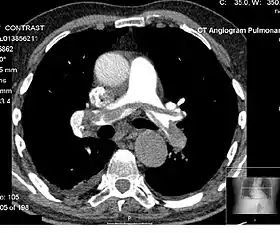

Contrast CT

Contrast CT is X-ray computed tomography (CT) using radiocontrast. Radiocontrasts for X-ray CT are, in general, iodine-based types.[1] This is useful to highlight structures such as blood vessels that otherwise would be difficult to delineate from their surroundings. Using contrast material can also help to obtain functional information about tissues. Often, images are taken both with and without radiocontrast. CT images are called precontrast or native-phase images before any radiocontrast has been administrated, and postcontrast after radiocontrast administration.[2]

Angiography

CT angiography is a contrast CT taken at the location and corresponding phase of the blood vessels of interest, in order to detect vascular diseases. For example, an abdominal aortic angiography is taken in the arterial phase in the abdominal level, and is useful to detect for example aortic dissection.[10]